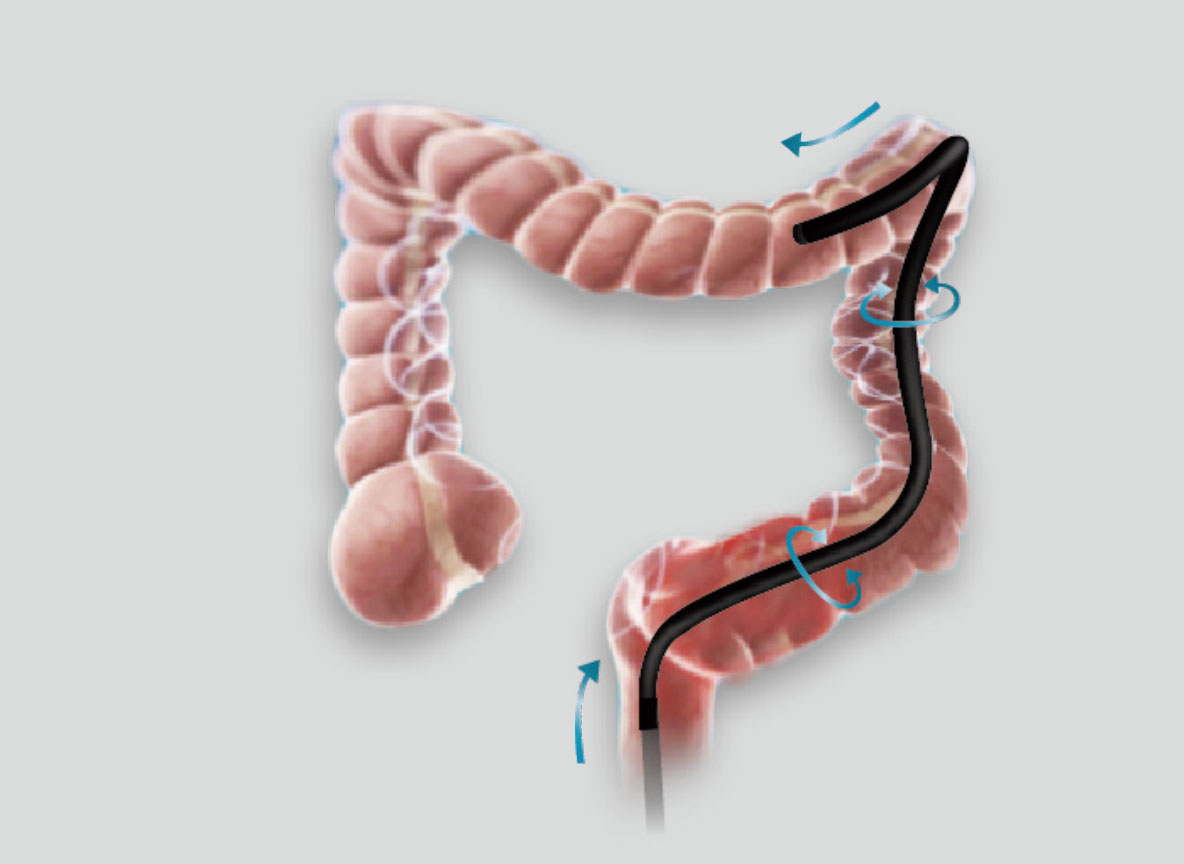

优秀的操控性和进镜性能

• 大弯曲角度

弯曲角度大,方便观察食管下段贲门、胃底部等难以观察到的部位,减少盲区。

• 高传导性分段硬度插入设计

带来镜体插入及诊疗新体验。

• 轻量化手柄

操作部轻量化设计,按钮布局合理,操作便捷。

• 辅助送水功能

在临床操作中,时刻保持黏膜清洁和视野清晰,更快寻找出血点,满足临床治疗。